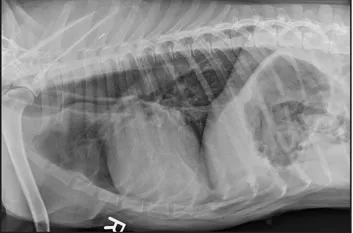

CASE 1.1 A 7-year-old neutered male Labrador Retriever who was hit by a car. You obtain these thoracic radiographs: Figs. 1.1a, b, left and right lateral projections, respectively; Figs. 1.1c, d, ventrodorsal and dorsoventral projections, respectively.

1.1a

1.1b

1.1c

1.1d